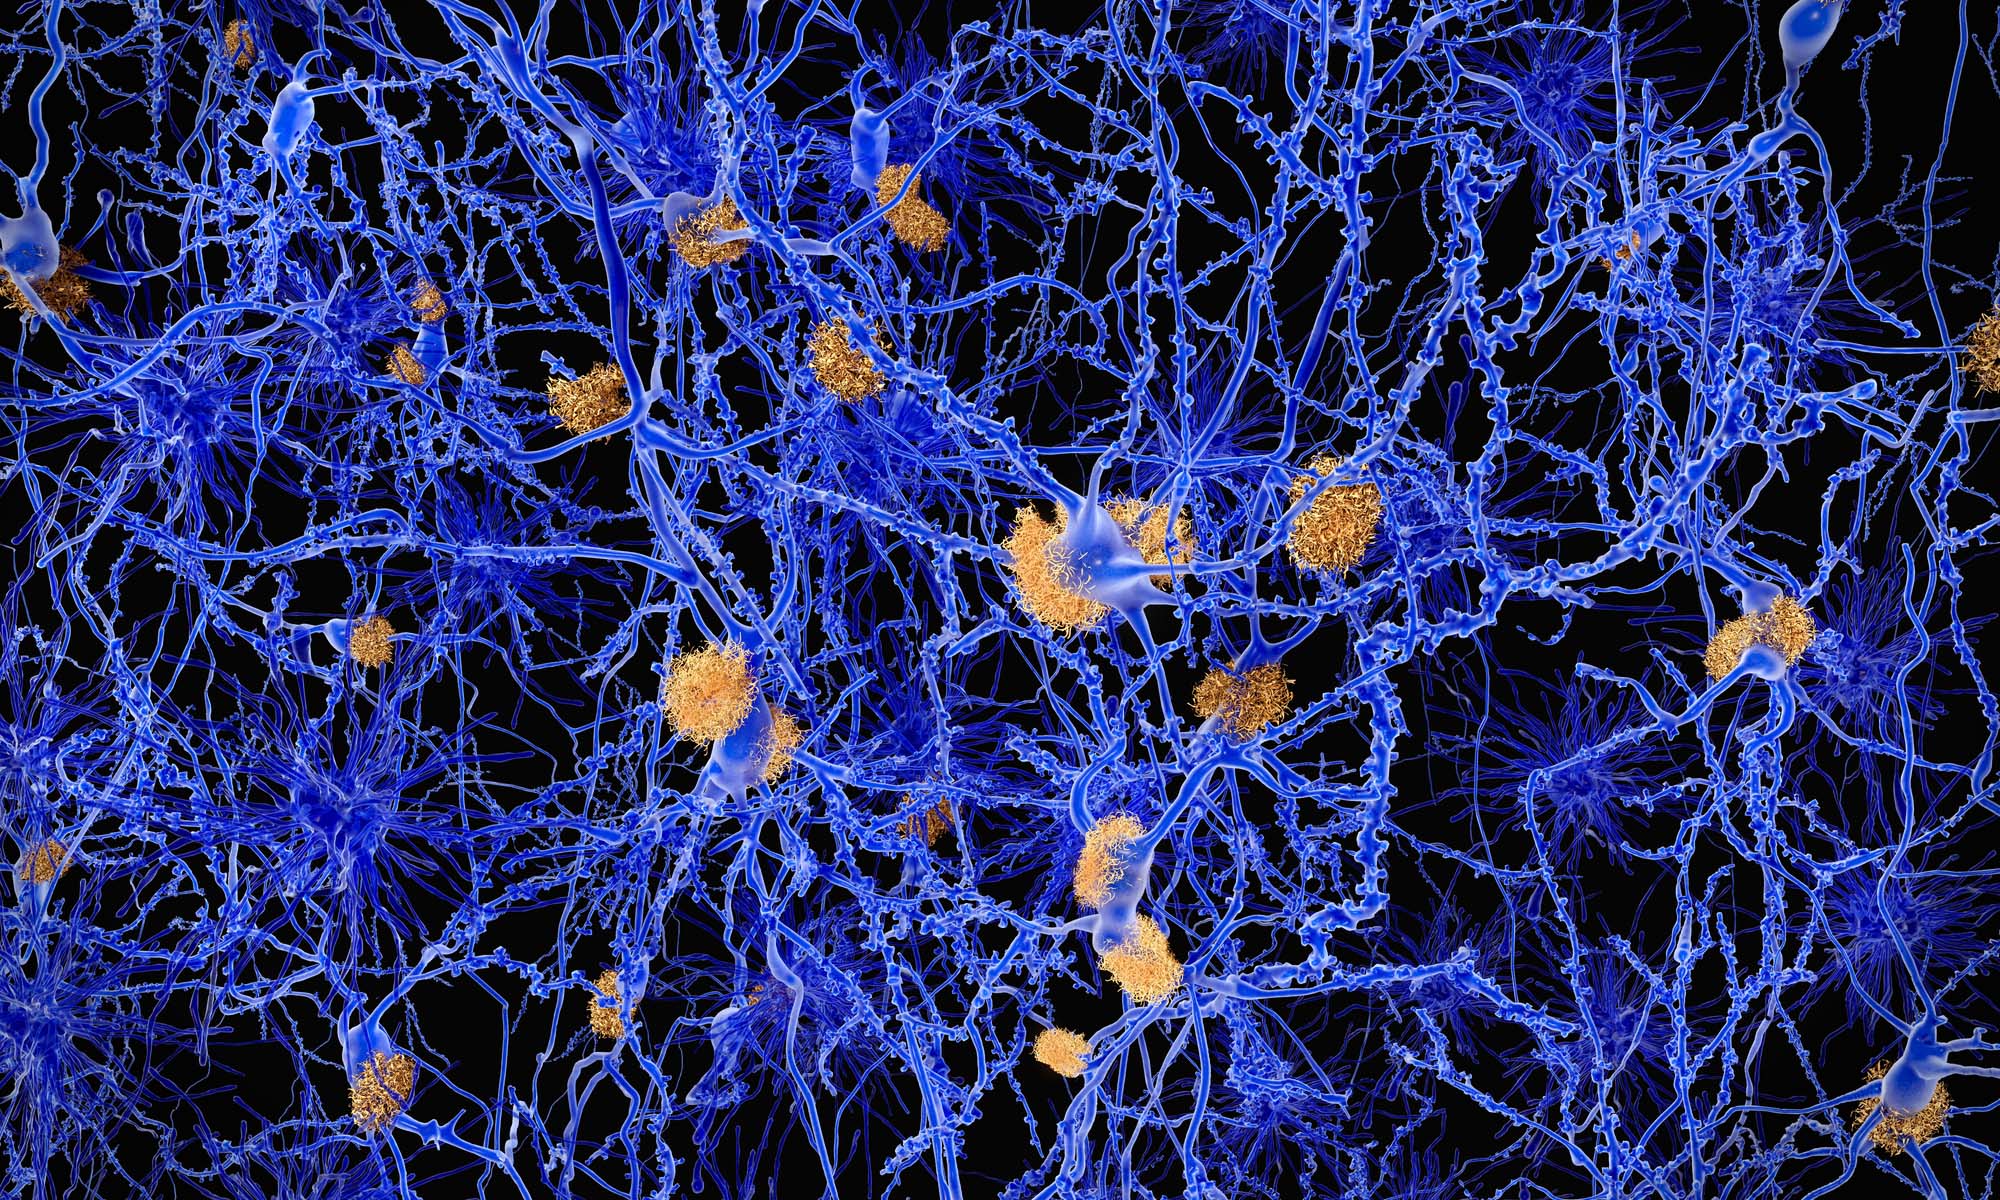

Image showing neurons with amyloid plaques. Neurons with amyloid plaques, indicators of Alzheimer's disease.

While the cause of Alzheimer’s disease remains a mystery, amyloid plaques that are toxic to brain cells are known indicators of the disease.

The new research showed these plaques start in the same place and spread in the same way in the brains of people with obstructive sleep apnea, as in those with Alzheimer’s.

In Alzheimer’s disease, plaques and tangles first appear in a nearby cortical area and then move into the hippocampus, before spreading to the rest of the cortex.

While the study found both plaques and tangles in the brains of people with sleep apnea, the plaques showed a stronger association with severe sleep apnea.